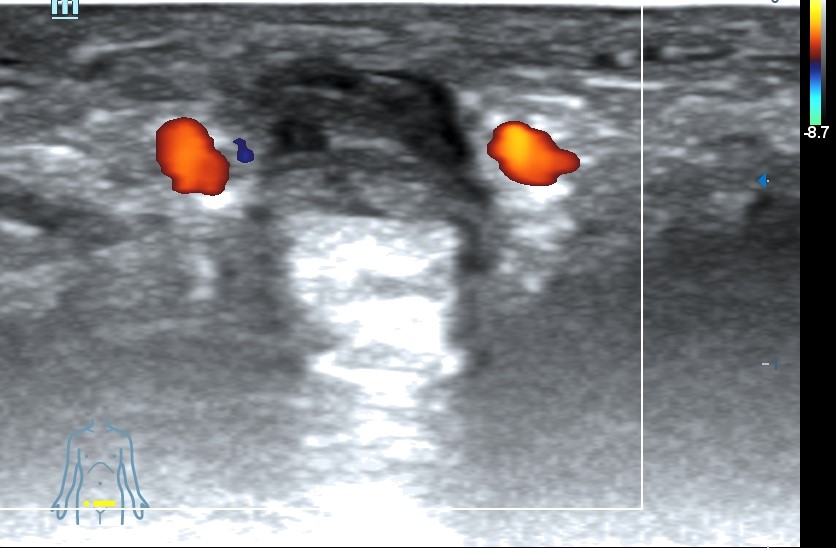

Ecografía clínica pene: se visualiza vena dorsal rellena de material hipoecogénico heterogéneo, no compresible, no flujo con Doppler color.

Diagnóstico: Trombosis vena dorsal del pene.